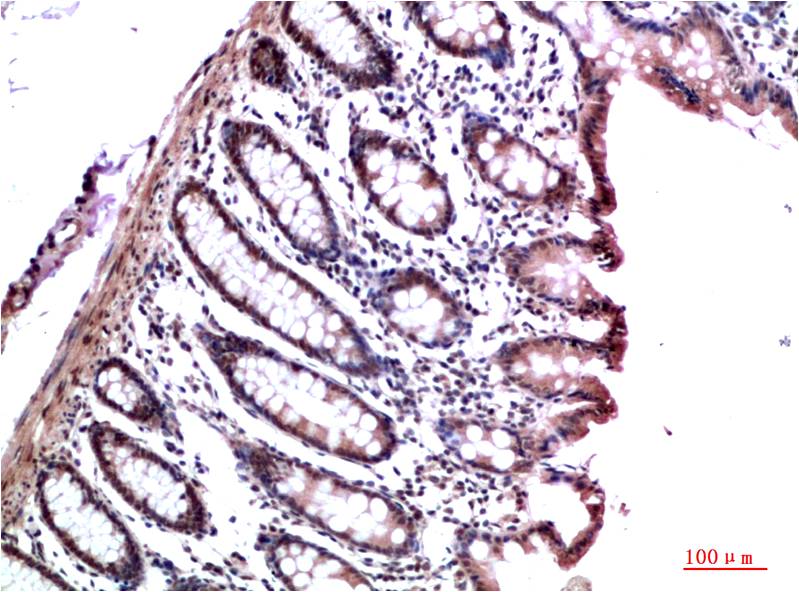

Immunohistochemistry analysis of paraffin-embedded Human Colon Carcinoma Tissue using HP1 gamma antibody.High-pressure and temperature Sodium Citrate pH 6.0 was used for antigen retrieval.